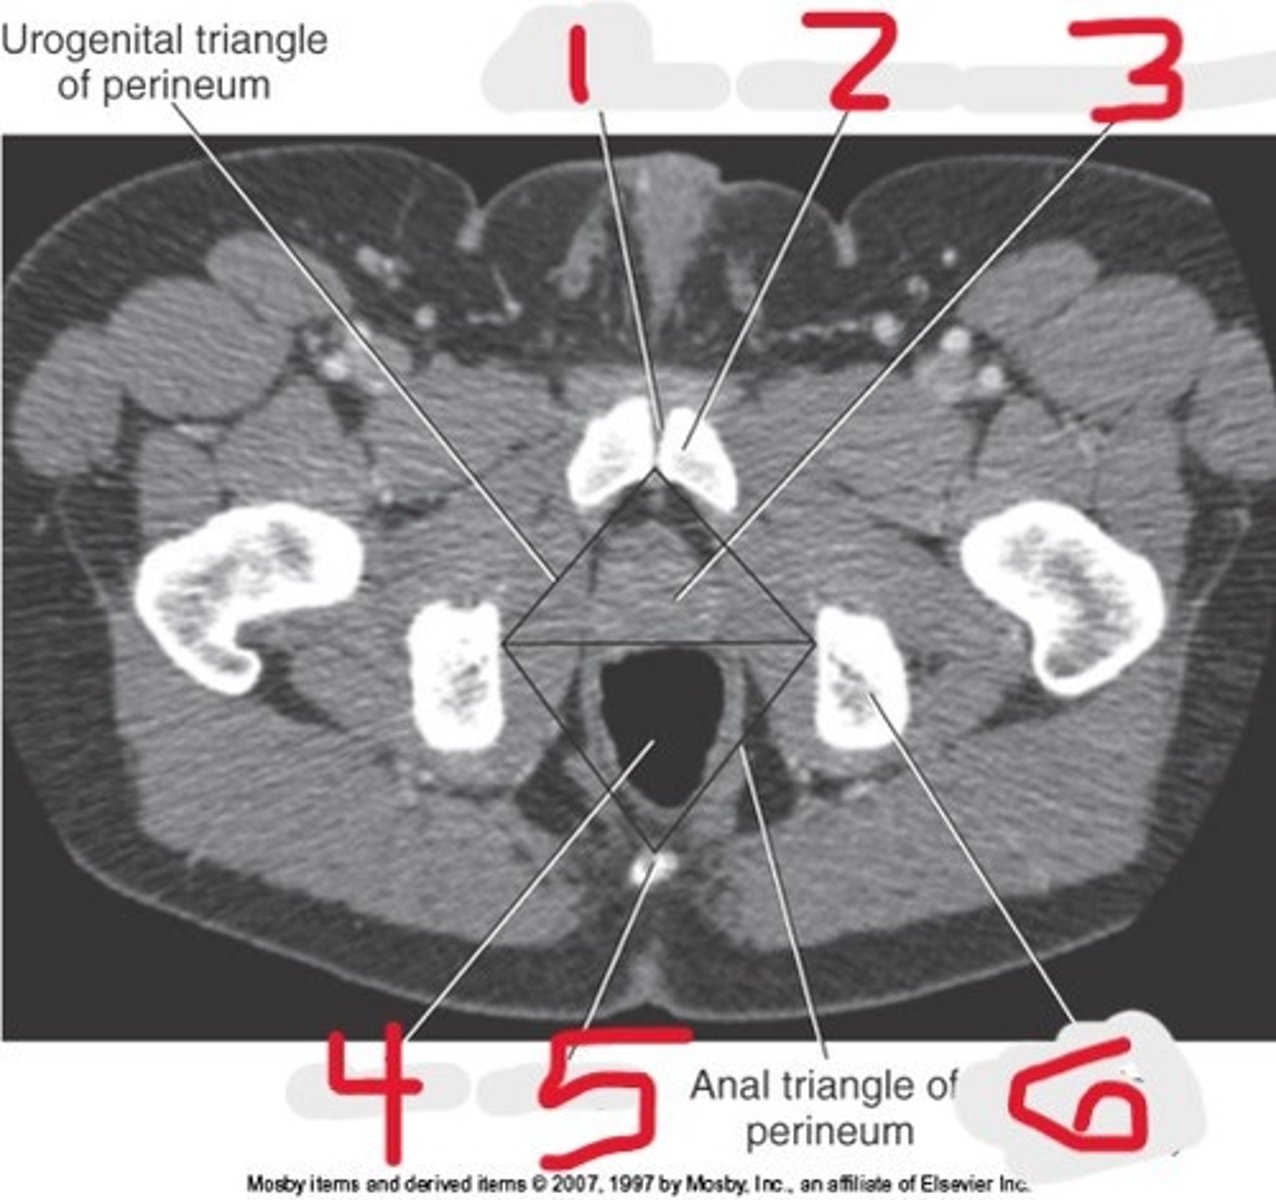

1) Body of pubic bone

2) Pubic symphysis

3) Greater trochanter

4) Anus

5) Ischial tuberosity

Name all numbered structures